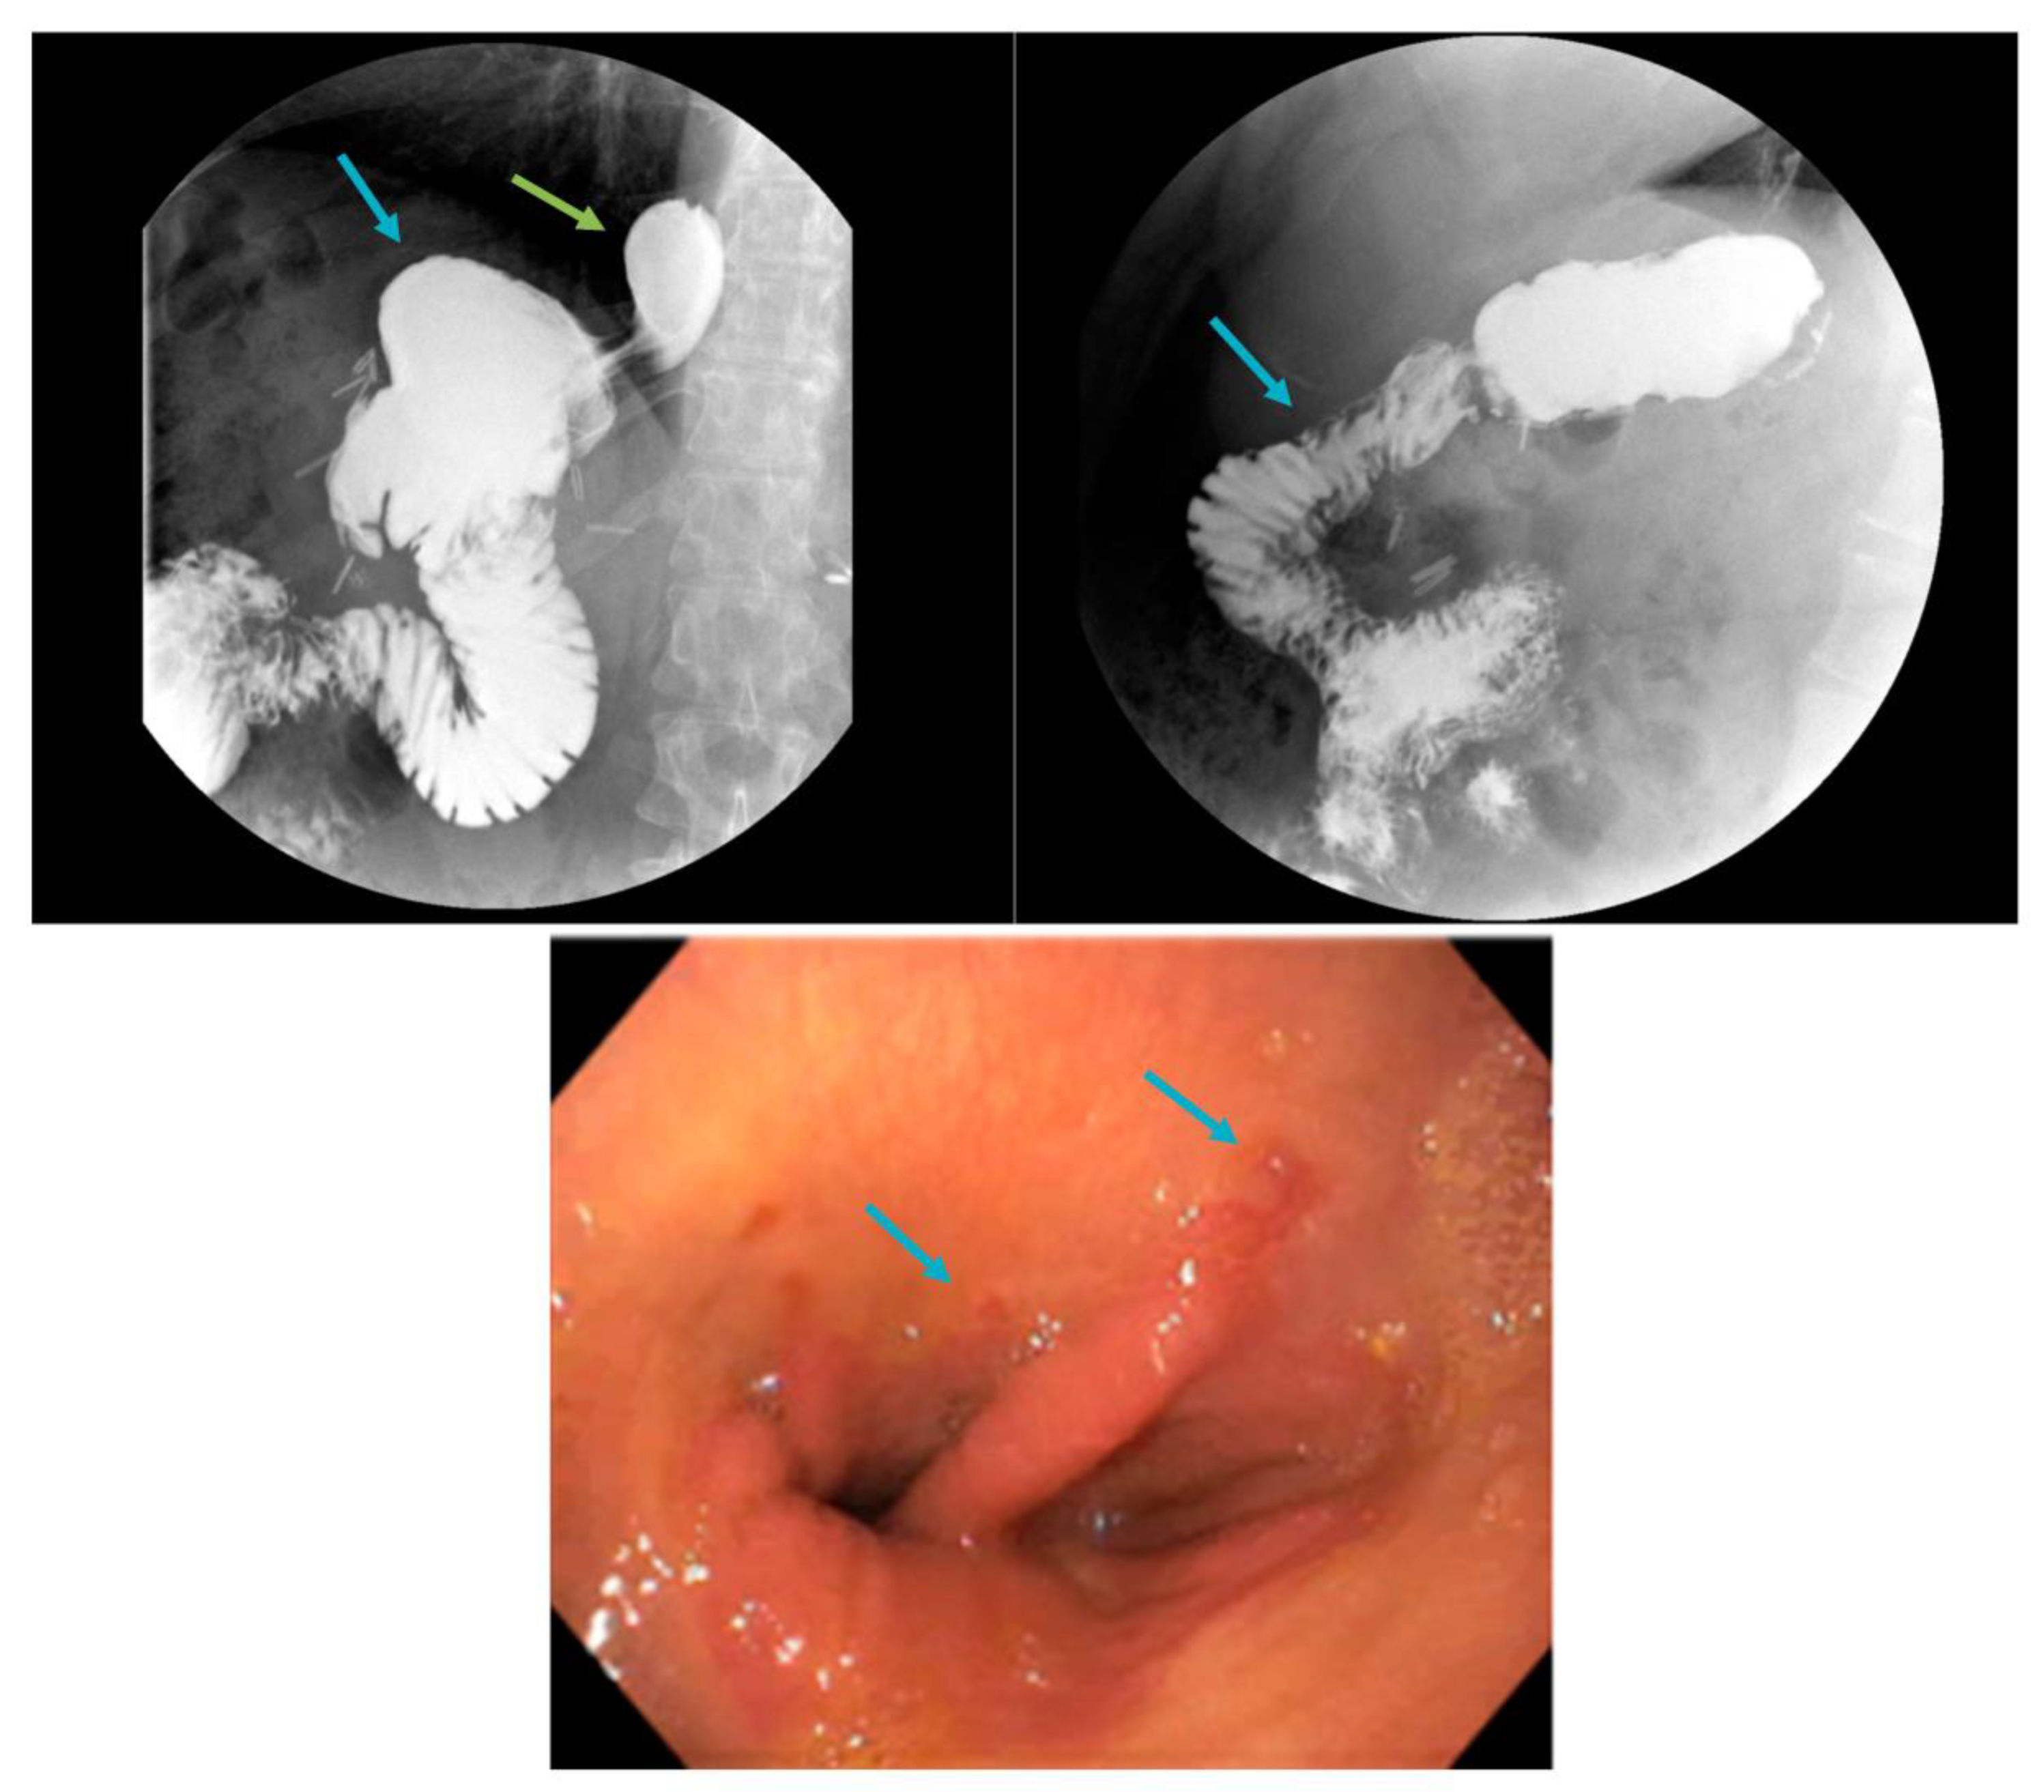

- Levy, J.L.; Levine, M.S.; E Rubesin, S.; Williams, N.N.; Dumon, K.R. Stenosis of gastric sleeve after laparoscopic sleeve gastrectomy: Clinical, radiographic and endoscopic findings. Br. J. Radiol. 2018, 91, 20170702. [Google Scholar] [CrossRef]

- Chang, S.H.; Popov, V.B.; Thompson, C.C. Endoscopic balloon dilation for treatment of sleeve gastrectomy stenosis: A systematic review and meta-analysis. Gastrointest. Endosc. 2020, 91, 989–1002.e4. [Google Scholar] [CrossRef]

- Mazer, L.; Yu, J.X.; Bhalla, S.; Platt, K.; Watts, L.; Volk, S.; Schulman, A.R. Pneumatic Balloon Dilation of Gastric Sleeve Stenosis Is Not Associated with Weight Regain. Obes. Surg. 2022, 32, 1–6. [Google Scholar] [CrossRef]

- Dhorepatil, A.S.; Cottam, D.; Surve, A.; Medlin, W.; Zaveri, H.; Richards, C.; Cottam, A. Is pneumatic balloon dilation safe and effective primary modality of treatment for post-sleeve gastrectomy strictures? A retrospective study. BMC Surg. 2018, 18, 52. [Google Scholar] [CrossRef]

- Kurien, R.; Menon, S. Balloon dilation in sleeve gastrectomy stenosis: A simple solution to an occasionally tricky problem. Gastrointest. Endosc. 2020, 91, 1003–1004. [Google Scholar] [CrossRef]

- Tsai, Y.-N.; Wang, H.-P.; Huang, C.-K.; Chang, P.-C.; Lin, I.-C.; Tai, C.-M. Endoluminal stenting for the management of leak following sleeve gastrectomy and loop duodenojejunal bypass with sleeve gastrectomy. Kaohsiung J. Med. Sci. 2018, 34, 43–48. [Google Scholar] [CrossRef]

- Chung, Y.; Park, D.G.; Kim, Y.J. Endoscopic Management of Staple Line Leak after Bariatric Surgery: Surgeon’s Perspective. Clin. Endosc. 2021, 54, 805–809. [Google Scholar] [CrossRef]

- Vilallonga, R.; Sanchez-Cordero, S.; Umpiérrez Mayor, N.; Molina, A.; Cirera de Tudela, A.; Ruiz-Úcar, E.; Carrasco, M.A. GERD after Bariatric Surgery. Can We Expect Endoscopic Findings? Medicina 2021, 57, 506. [Google Scholar] [PubMed]